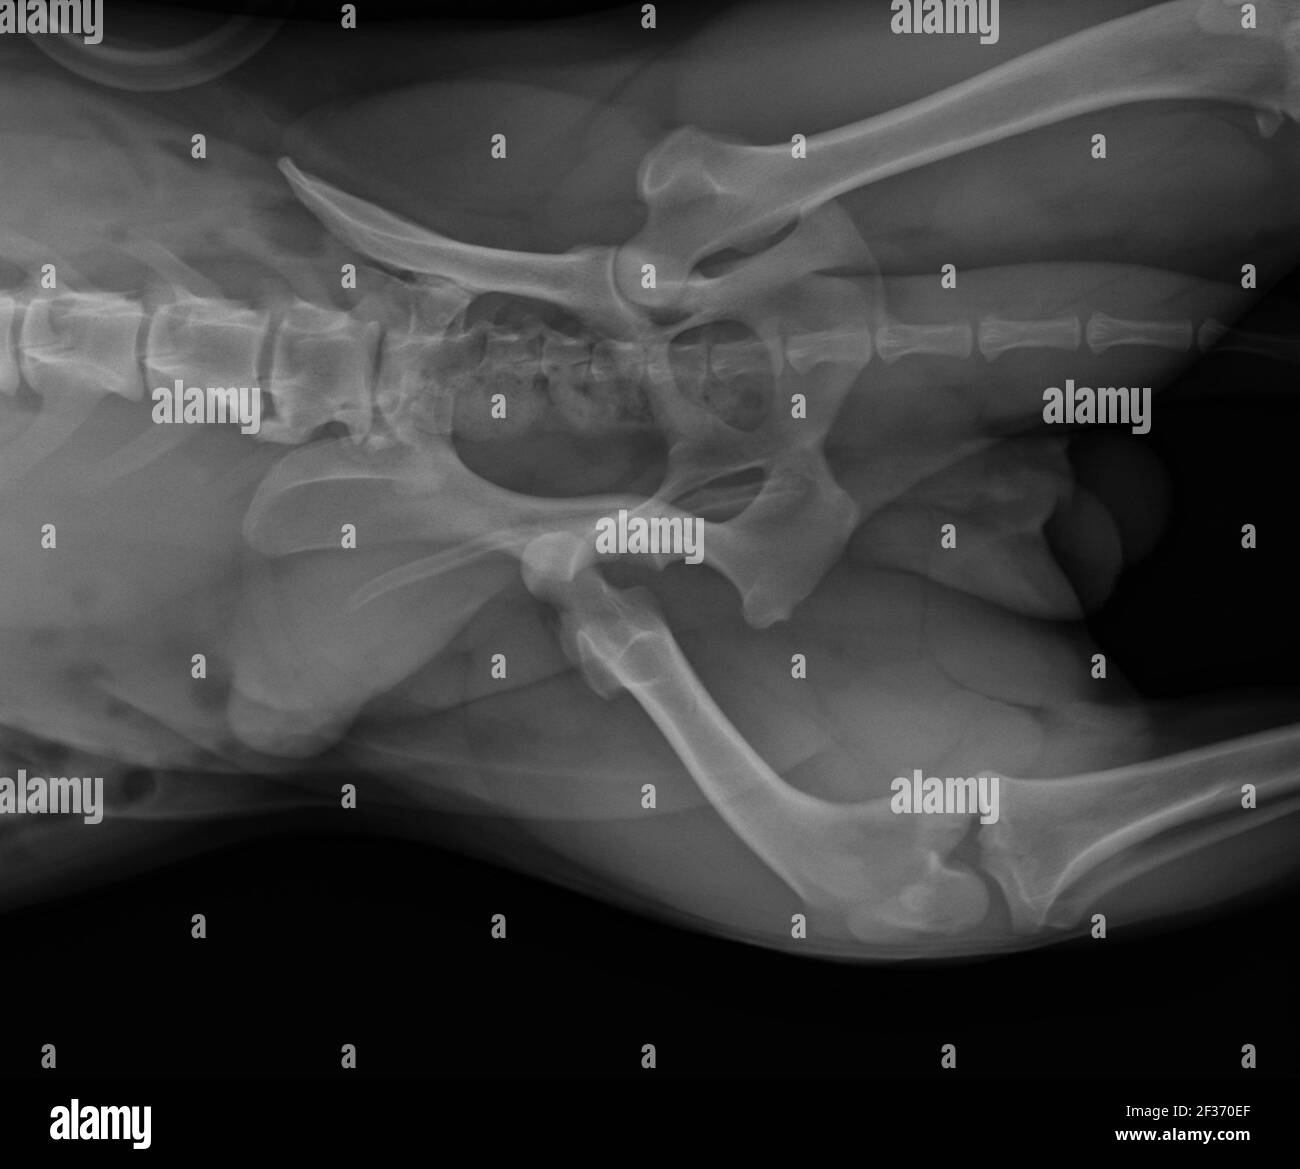

Dog X Ray Showing Hip Luxation Right Leg. Ventral View Stock Photo Alamy Canine Hip Xray Chd is diagnosed by a combination of two. evaluation of congenital disorders (eg, canine or feline hip dysplasia). canine hip dysplasia (cho) is a highly prevalent multifactorial disorder. 8,9 radiographs are recommended for dogs aged 5 to 10 months with hip joint laxity and clinical signs of hip dysplasia (e.g., lameness, bunny hopping, gait abnormalities, pain on manipulation).. Canine Hip Xray.